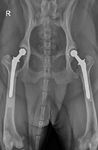

Hip dysplasia is the most common developmental orthopedic disease in dogs. First described in the 1930's, it continues to affect millions of dogs worldwide. Large breed dogs are most commonly diagnosed, however small breed dogs and cats also are affected.